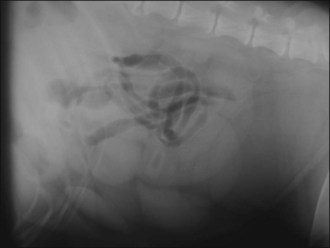

Aggressive intravenous fluid resuscitation with an isotonic crystalloid solution was commenced and morphine (0.3 mg/kg slow i.v.) administered. Abdominal ultrasound revealed the presence of enlarged uterine horns distended with hypoechoic fluid consistent with pyometra and peritoneal fluid was detected (Figure 29.1).

Figure 29.1 Ultrasound image of pyometra showing enlarged uterine horns distended with hypoechoic fluid; the urinary bladder is also visible.